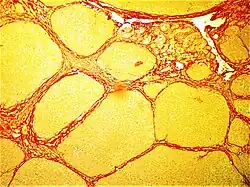

| Micrograph of a heart showing fibrosis (yellow – left of image) and amyloid deposition (brown – right of image). Stained using Movat's stain. | |